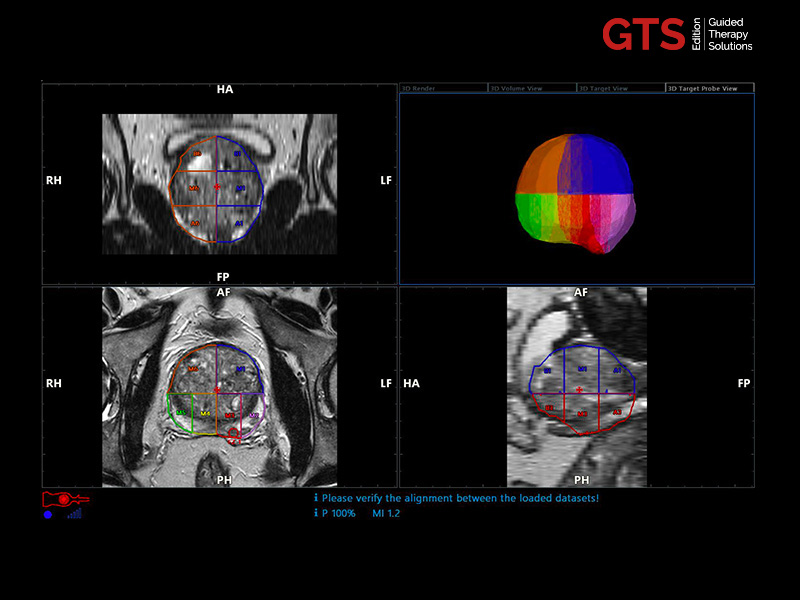

Expert users and beginners can now achieve a heightened degree of simplicity and precision by using UroFusion, Esaote’s cutting-edge fusion imaging solution that makes the most of the combination of US and MR or PET modalities.

By harnessing Augmented Insight™ (A.I.) technology, our dedicated solution enhances workflow efficiency by Automating MR Prostate Contouring & Segmentation with instant and automatic US-MR Synchronization, applied to both transperineal (TPUS) and transrectal (TRUS) prostate biopsy approaches.

Using UroFusion, clinicians will benefit from our intuitive tools to fasten the fusion procedures: the automatic prostate contouring and biopsy sample mapping are certainly the most impressive.

UroFusion seamlessly offers the ability to combine different mpMRI series, facilitating the identification of suspicious prostate lesions.

mpMRI targeting phase of PI-RADS 5 peripheral lesion